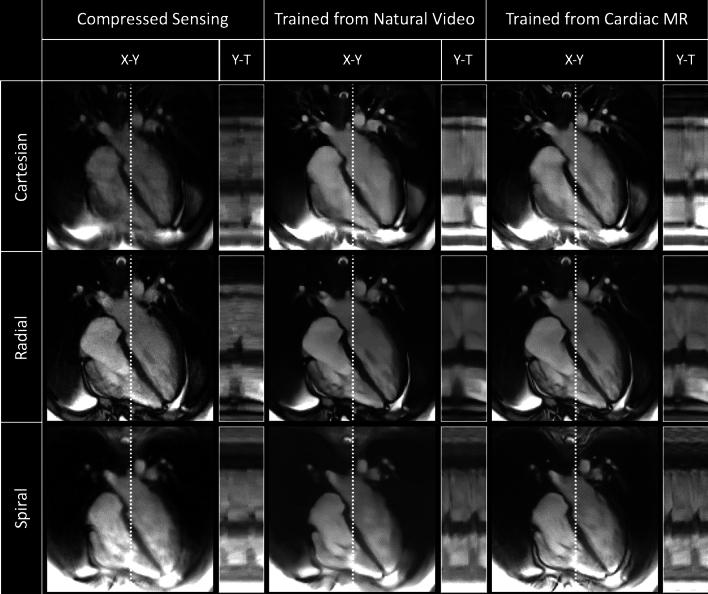

To develop and assess a deep learning (DL) pipeline to learn dynamic MR image reconstruction from publicly available natural videos (Inter4K). Learning was performed for a range of DL architectures (VarNet, 3D UNet, FastDVDNet) and corresponding sampling patterns (Cartesian, radial, spiral) either from true multi-coil cardiac MR data (N = 692) or from synthetic MR data simulated from Inter4K natural videos (N = 588). Real-time undersampled dynamic MR images were reconstructed using DL networks trained with cardiac data and natural videos, and compressed sensing (CS). Differences were assessed in simulations (N = 104 datasets) in terms of MSE, PSNR, and SSIM and prospectively for cardiac cine (short axis, four chambers, N = 20) and speech cine (N = 10) data in terms of subjective image quality ranking, SNR and Edge sharpness. Friedman Chi Square tests with post-hoc Nemenyi analysis were performed to assess statistical significance. In simulated data, DL networks trained with cardiac data outperformed DL networks trained with natural videos, both of which outperformed CS (p < 0.05). However, in prospective experiments DL reconstructions using both training datasets were ranked similarly (and higher than CS) and presented no statistical differences in SNR and Edge Sharpness for most conditions.The developed pipeline enabled learning dynamic MR reconstruction from natural videos preserving DL reconstruction advantages such as high quality fast and ultra-fast reconstructions while overcoming some limitations (data scarcity or sharing). The natural video dataset, code and pre-trained networks are made readily available on github.

开发并评估了一种深度学习(DL)管道,用于从公开的自然视频(Inter4K)中学习动态磁共振图像重建。学习是针对一系列 DL 架构(VarNet、3D UNet、FastDVDNet)和相应的采样模式(笛卡尔、径向、螺旋)进行的,这些架构和模式既可以从真实的多通道心脏磁共振数据(N=692)中获取,也可以从从 Inter4K 自然视频模拟的合成磁共振数据(N=588)中获取。使用基于心脏数据和自然视频训练的 DL 网络以及压缩感知(CS)技术重建实时欠采样动态磁共振图像。在模拟(N=104 个数据集)中,从均方误差(MSE)、峰值信噪比(PSNR)和结构相似性指数(SSIM)方面评估了差异,并前瞻性地从心脏电影(短轴、四腔室,N=20)和语音电影(N=10)数据方面评估了主观图像质量排名、信噪比(SNR)和边缘锐度。采用 Friedman Chi Square 检验和事后 Nemenyi 分析评估了统计学意义。在模拟数据中,基于心脏数据训练的 DL 网络优于基于自然视频训练的 DL 网络,而这两者都优于 CS(p<0.05)。然而,在前瞻性实验中,使用这两个训练数据集的 DL 重建被评为相似(且高于 CS),并且在大多数情况下,在 SNR 和边缘锐度方面没有统计学差异。该开发的管道能够从自然视频中学习动态磁共振重建,保留了 DL 重建的优势,例如高质量的快速和超快速重建,同时克服了一些限制(数据稀缺或共享)。自然视频数据集、代码和预训练网络都可以在 github 上轻松获得。